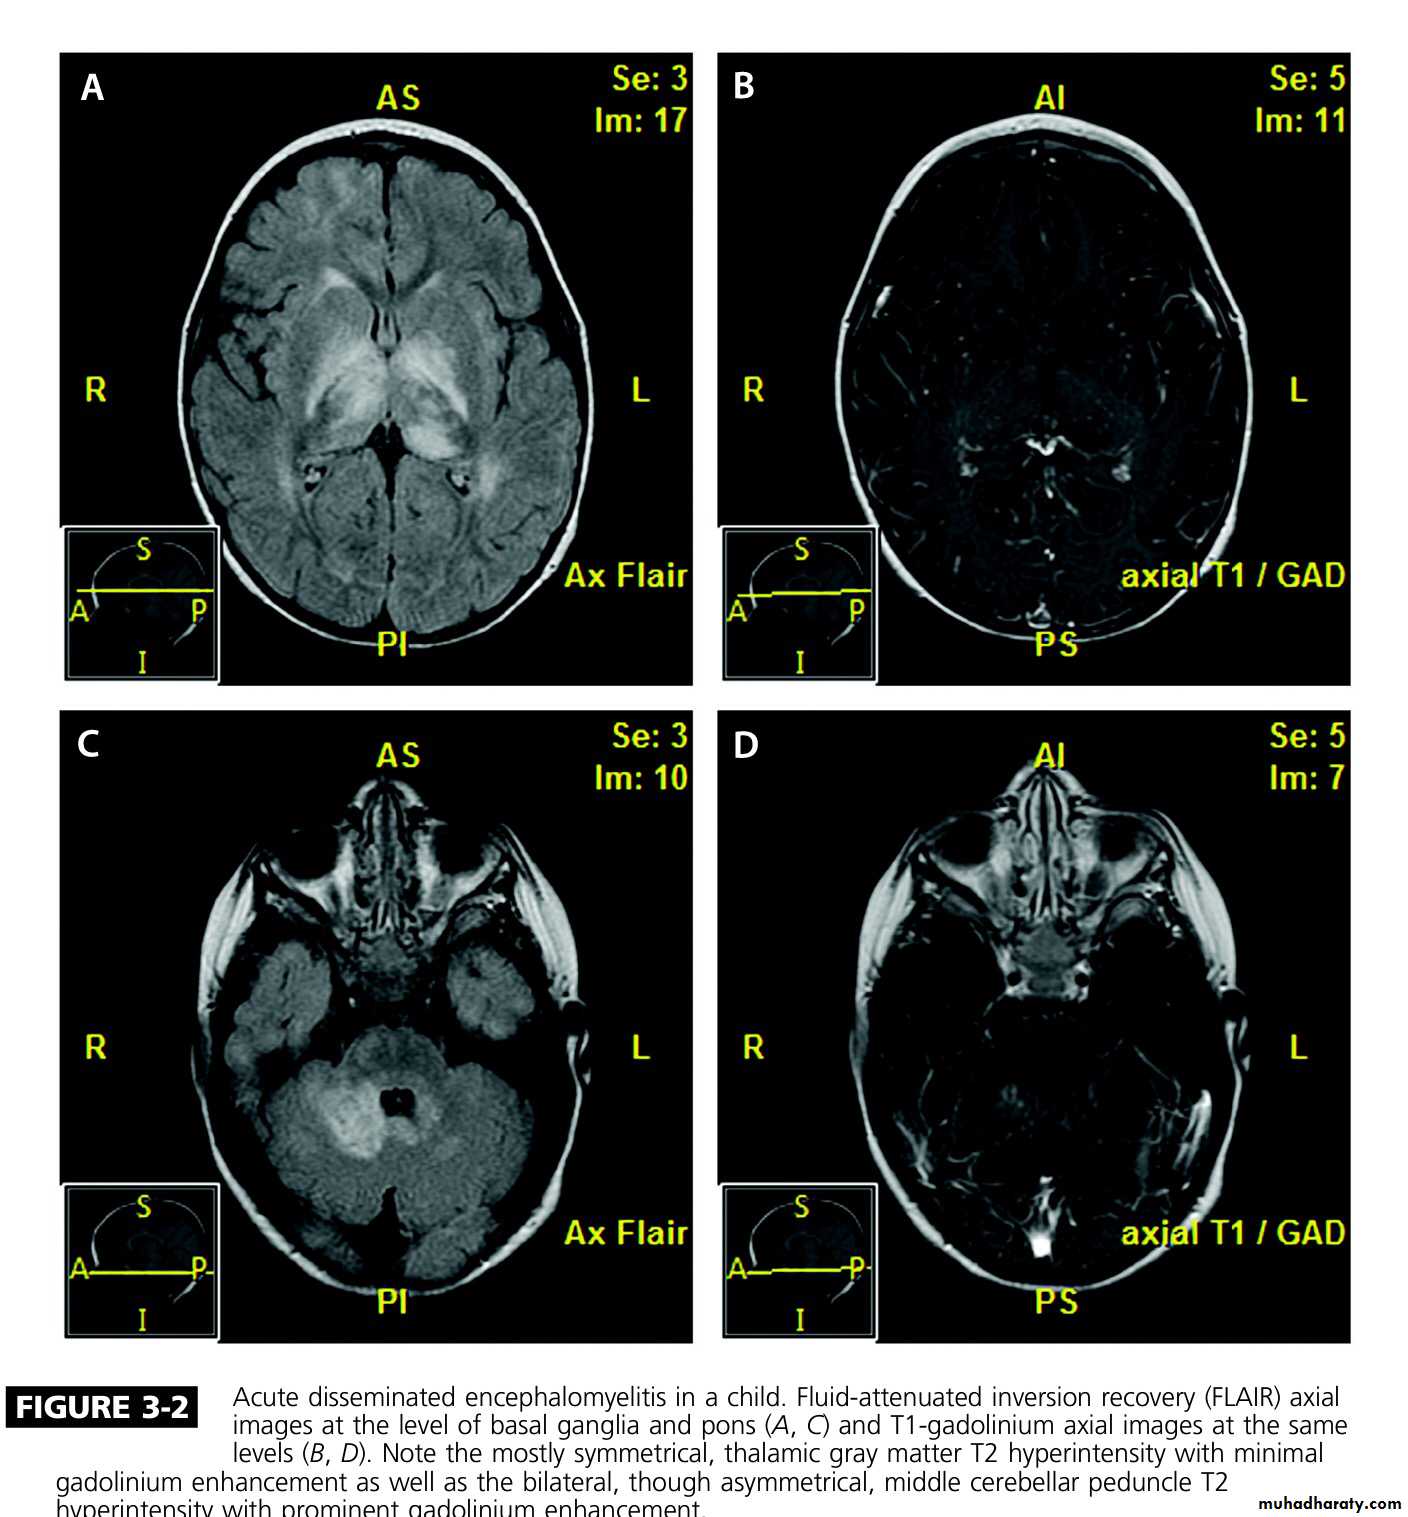

Acute disseminated encephalomyelitis (ADEM)

Acute disseminated encephalomyelitis

This is an acute monophasic demyelinating condition in which there are areas of perivenous demyelination widely disseminated throughout the brain and spinal cord. The illness may apparently arise spontaneously but often occurs a week or so after a viral infection, especially measles and chickenpox, or following vaccination, suggesting that it is immunologically mediated.

MRI shows multiple high-signal areas in a pattern similar to that of MS, although often with large confluent areas of abnormality. The CSF may be normal or show an increase in protein and lymphocytes (usually 200 cells/L) . The clinical picture may be very similar to a first relapse of MS.